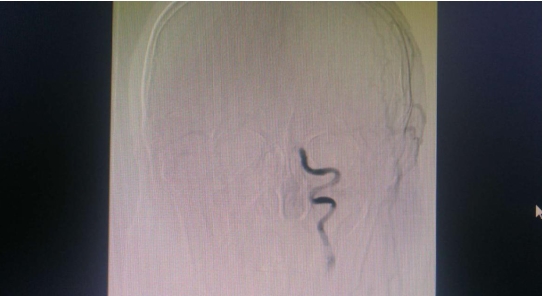

通过造影发现患者左侧颈内动脉闭塞 患者术后闭塞血管开通

患者朱先生,因“突发右侧肢体无力伴失语 5+小时”入石柱县人民医院神经内科治疗,入院患者查体不合作、嗜睡、不言语、右下肢未见活动,头颅 CT未见出血,脑MRI 提示左侧脑梗塞同时存在可挽救的半暗带,需要急诊行脑动脉造影检查。经患者家属同意后,我院医疗支援石柱分院的神经内科宋敏博士与石柱县人民医院神经内科主任李品军副主任医师按照脑卒中绿色通道流程迅速为患者进行了脑动脉造影检查,发现患者左侧颈内动脉C6段闭塞,立刻急诊实施闭塞血管球囊扩张+动脉支架置入术,短时间内完成了闭塞血管开通。术后患者右侧肢体力量恢复明显,其他症状也有明显改善。